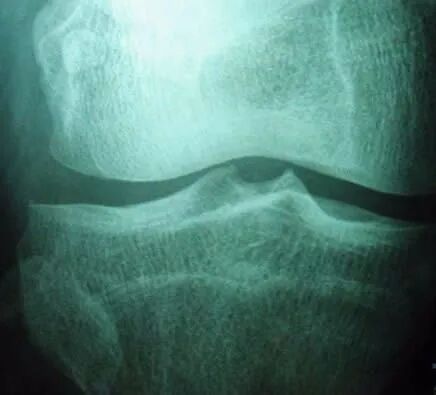

如果膝关节骨质增生严重

骨性关节炎实际上